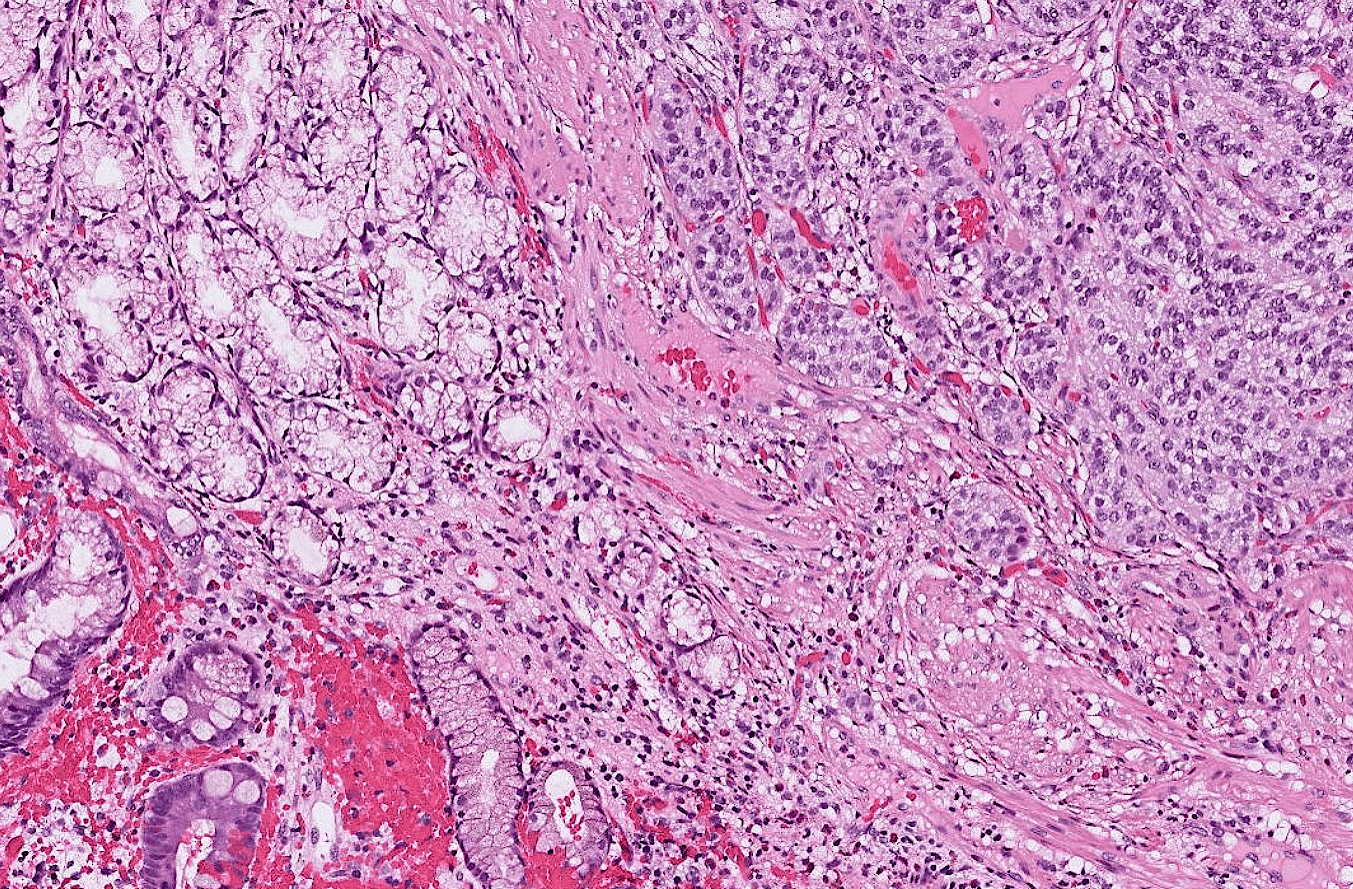

lung adenocarcinoma

colon cancer

endometrial cancer